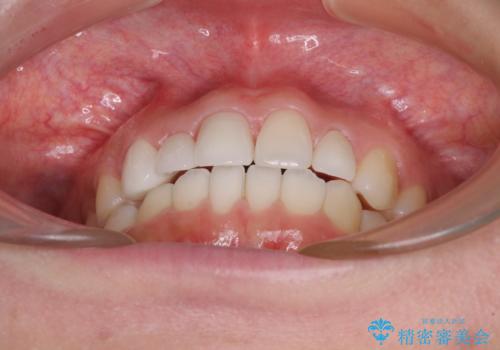

矯正治療後には欠損部はオールセラミックブリッジに、矮小歯はオールセラミッククラウンにて補綴することとしました。

ワイヤー矯正により、インビザラインよりも早く、歯軸の向きもコントロールしながら移動させることができました。